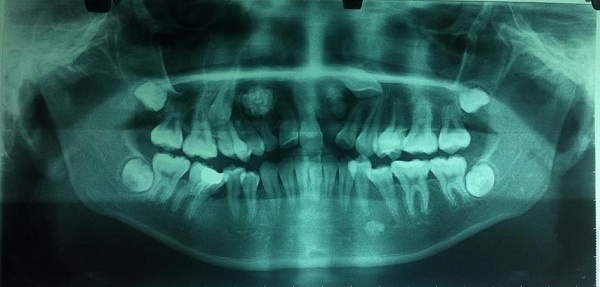

| Phim panaroma toàn cảnh răng của bệnh nhân, cho thấy u răng, răng ngầm tương ứng bên phải và bên trái trên phim. |

Sau khi thăm khám và hỏi bệnh, ThS. Trung đã tư vấn cho bố mẹ bệnh nhân nên đưa con đi chụp các phim chuyên khoa để phát hiện thêm trên phim tại chỗ, phim panorama (toàn cảnh). Kết quả phát hiện trên phim X-quang thấy bệnh nhân có u răng 2 bên và 2 răng ngầm, nên các bác sĩ tại khoa Răng Hàm Mặt đã chỉ định mổ lấy u răng và lấy răng ngầm cho cháu.